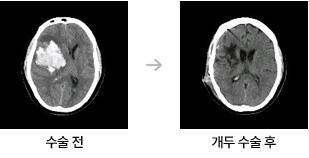

- 수술: 상황에 따라 출혈을 제거하고, 필요한 경우 뇌의 압력을 줄이기 위한 수술을 시행합니다.

- 회복 단계: 수술 후, 환자는 집중치료실에서 의식 상태를 면밀히 모니터링 받고, 회복 과정을 거칩니다.